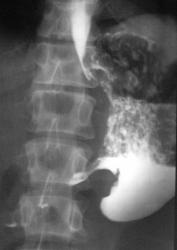

Окончательно можно сказать одно что идёт симметричное сужение просвета антрального отдела, рельеф слизистой не прослеживается, стенки регидны.

1- синдром сужения просвета пищеварительной трубки, а именно стойкое симметричное сужение, абсолютно на всех снимках и даже после приёма "шипучки" и не говоря уже про введения атропина

2- синдром изменения слизистой, в месте где идёт сужение мы рельефа слизистой не наблюдаем, ну а первое что меня насторожило это конвергенция складок в проекции синуса желудка

3- это не мало важный признак, изменение эластичности и перестальтики полого органа, видно на всех снимках симптом регидности стенок антрального отдела;

Аналогично и у автора представленных снимочков, антральный отдел сужен с переходом на превратник, а так же процесс идет по малой кривизне, вот только не понятно с кардиальным отделом, он кажется тоже деформирован. По степени же стенозаснимки надо обязательно сделать через 12 и 24 часа что бы решить есть или нет декомпенсированный стеноз. В этом слачае видно что в желудке много слизи, смею предположить о декомпенсированном стенозе.

Уважаемые коллеги! Спасибо за внимание к представленным мною снимкам.У пациента инфильтративный рак с полным стенозом антрального отдела и поражением тела желудка а также с переходом на кардиальный отдел.Валентин Львович Вы правы поповоду интермедиарного слоя - это остатки непереваренной пищи которые взболтались после исследования в горизонтальном положении а эвакуации не было вообще

Уважаемый v1tal! Спасибо за ваши снимки и комментарии.Вы полностью правы стеноз полный а кардиальный отдел тоже поражен